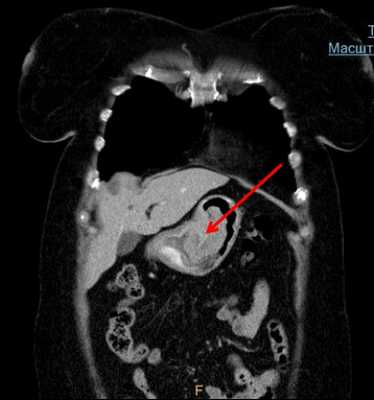

С целью выяснения степени распространенности опухолевого роста в средостении, оценки местного распространения опухоли по лимфатическим сосудам, а также для обнаружения возможных отдалённых метастазов возможно применение компьютерной томографии (КТ). Бронхоскопию выполняют для оценки возможности прорастания опухоли в трахеобронхиальное дерево. В диагностически сложных случаях возможно применение медиастиноскопии.

![КТ грудной клетки. Выраженное циркулярное мягкотканное утолщение стенки пищевода в нижней трети]()